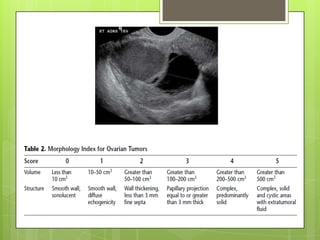

Ecografía

 En general, los tumores malignos son

multiloculados, sólidos o ecogénicos,

grandes (>5 cm) y tienen tabiques

gruesos con áreas de nodularidad.

 Otras características incluye

proyecciones papilares,

neovascularización, demostrada por flujo

Doppler.

Amplia disponibilidad.

Costo.

Buena tolerabilidad de paciente.

Uso rutinario.

Cuando se usa sola, pierde sensibilidad

y valor predictivo positivo.

Morfología, lateralidad, volumen,

estructura, septos.

Ecografía transvaginal